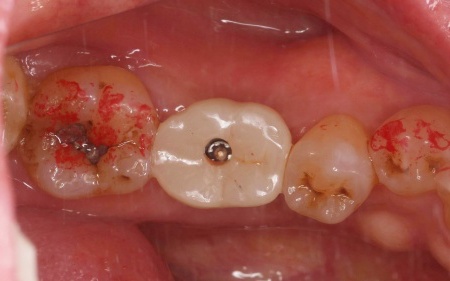

治療前

治療中